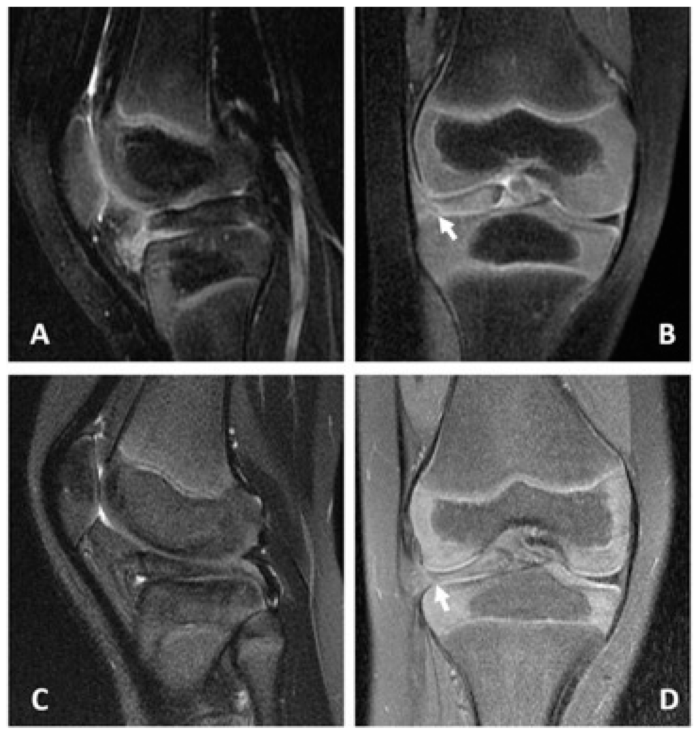

A bucket handle meniscus tear is easily detected on MRI. An indentation on the surface of the anterior horn characterizes it.